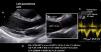

Sistolic volume (SV) assessment (Fig. 2)It can be performed using the velocity time integral (VTI) and the diameter of the left ventricular outflow tract (LVOT).

Estimation of systolic volume (SV) and cardiac output (CO) through the velocity time integral (VTI) and radius (r) of the left ventricular outflow tract (LVOT). A: left parasternal view of the left ventricle in systole. B: zoomed LVOT. C: pulsed-wave Doppler LVOT 5C apical. D: calculations.

VTI LVOT<11cm is correlated with a cardiac index<2L/min.17,18